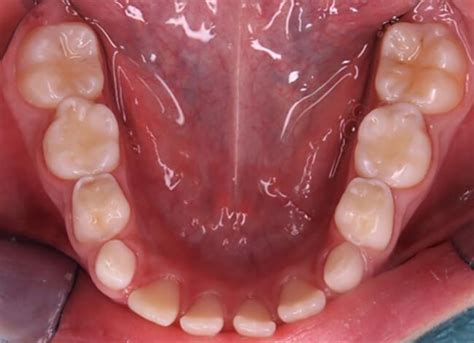

La distribución de la erosión dental no es uniforme dentro de los arcos dentarios. En niños y adolescentes los dientes anteriores maxilares, especialmente las superficies palatinas y los primeros molares permanentes, son los más frecuentemente afectados.

Desde el punto de vista clínico se describen ciertas características comunes, donde las lesiones por erosión dental se presentan tanto en zonas linguales como vestibulares, especialmente en el tercio gingival, como pequeñas depresiones o lesiones superficiales, más anchas que profundas, con forma de disco, cuchara o irregular. También se caracterizan por tener márgenes lisos y poco definidos, mostrando la superficie del esmalte pulida y sin brillo. Cuando se presenta en zonas oclusales lo hace en forma de canaleta o pozos.